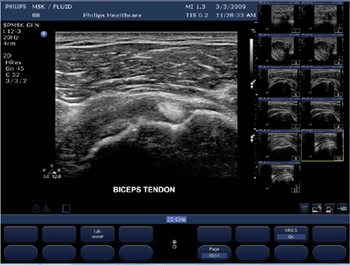

Miniaturization gives portable units functions once available only in cart-based systems.